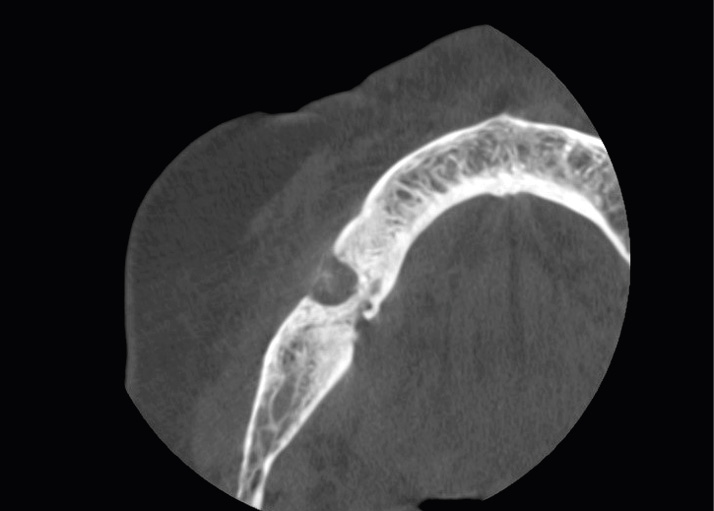

STRESZCZENIE: Terapia z użyciem bisfosfonianów i innych leków antyresorpcyjnych jest obecnie szeroko stosowana u pacjentów chorujących na osteoporozę. Mimo istotnych zalet w leczeniu choroby podstawowej pacjenci zostają włączeni do grupy ryzyka martwicy kości szczęk zależnej od leków (MRONJ). Celem pracy jest przedstawienie leczenia protetycznego i powikłań u pacjentki z MRONJ w wywiadzie. Wystąpienie MRONJ jest rzadkim, ale potencjalnie poważnym skutkiem ubocznym i istotne jest, by lekarze dentyści zapoznali się ze sposobami profilaktyki MRONJ oraz leczenia pacjentów w grupie ryzyka MRONJ.

SUMMARY: Therapy with bisphosphonates and other antiresorptive medicaments is nowadays widely recommended for patients with osteoporosis. There are various benefits of antiresorptive therapy. However, MRONJ is potentially a key risk that arises during treatment. Therefore, dental practitioners should properly assess and implement individual treatment plans as well as select dental procedures that minimize the risk of MRONJ. The purpose of this paper is to present a prosthodontic treatment and complications [...]